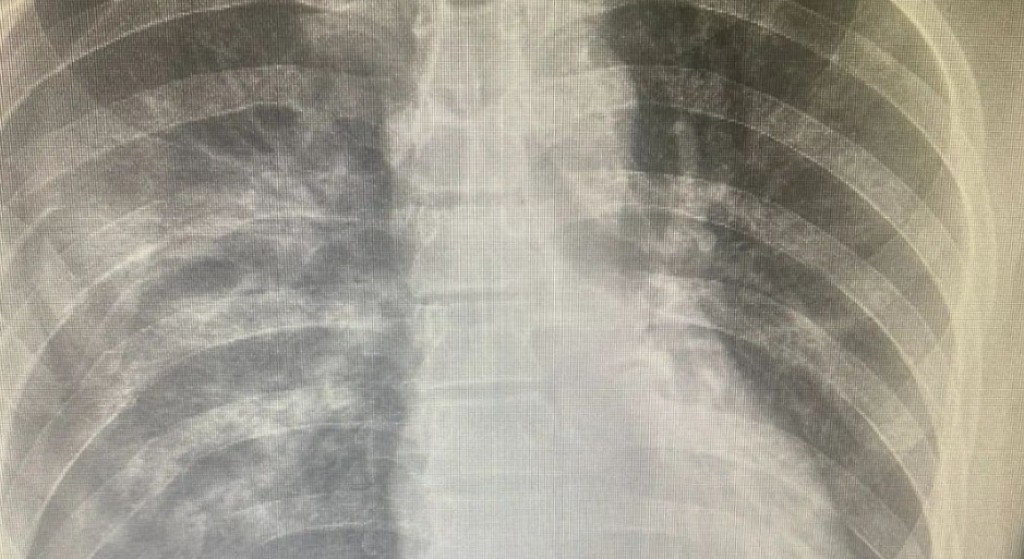

Врачи Центральной больницы Балхаша спасли жизнь пациенту, который поступил в медучреждение с тяжелой производственной травмой. Мужчину зажало между барабаном и конвейерной лентой, сообщают в ЦБ Балхаша.

Диагноз пациента - политравма, закрытый оскольчатый перелом 3, 4, 5, 6, 7, 8, 9, 10, 11 рёбер справа со смещением, пневмогемоторакс справа. Ушиб легкого. Обширная скальпированная рана в левой и в правой височно-теменной области с частичной травматической ампутацией правой ушной раковины. Травматическая ампутация дистальных фаланг 3, 4 пальцев правой кисти. Травматический шок 2 степени.

"Первую операцию проводил врач-хирург Андрей Пак, анестезиолог Мусамат Шадиметов. Состав бригады второй операции: хирург Максат Нуртазин, анестезиолог Рысбек Анафияұлы, ассистент - Зориг Сультимов. В итоге проведены четыре оперативных вмешательства", - говорят в больнице Балхаша.

В течение девяти дней пациент находился в отделении реанимации на искусственной вентиляции легких. Здесь за его жизнь боролись реаниматологи. В настоящее время пациент выписан домой, состояние его стабильное, угрозы для жизни нет.